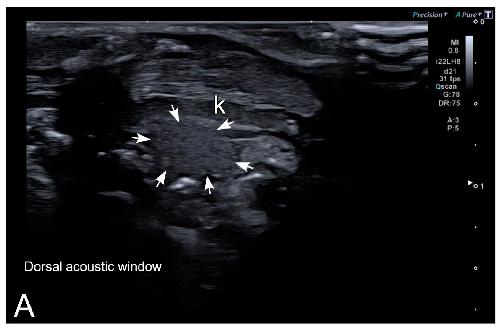

Sex Determination in Two Species of Anuran Amphibians by Magnetic Resonance Imaging and Ultrasound Techniques. , Ruiz-Fernández MJ, Jiménez S, Fernández-Valle E, García-Real MI, Castejón D, Moreno N , Ardiaca M, Montesinos A, Ariza S, González-Soriano J., Animals (Basel). November 18, 2020; 10 (11):